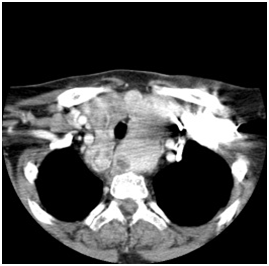

Figure 2 Axial view of mediastinal goiter.

Figure 3 Goiter extend below aortic arch to level of carina